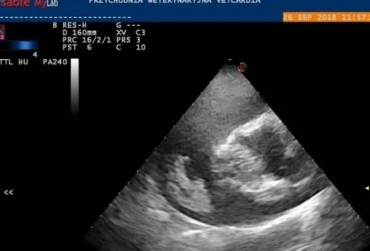

Echo serca z widoczną obecnością dużej liczby nicieni w prawym przedsionku serca (1)

16 kwietnia 2019

Wojciech Atamaniuk

Echo serca z widoczną obecnością dużej liczby nicieni w prawym przedsionku serca (3)

Echo serca z widoczną obecnością dużej liczby nicieni w prawym przedsionku serca (2)

Echo serca z widoczną obecnością dużej liczby nicieni w prawym przedsionku serca (4)